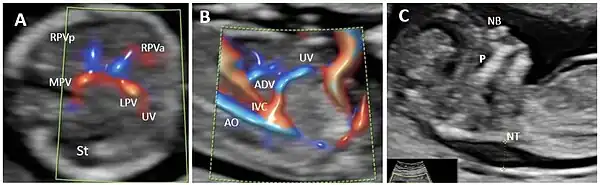

In the fetus, the ductus venosus ("DV"; Arantius' duct after Julius Caesar Aranzi[1]) shunts a portion of umbilical vein blood flow directly to the inferior vena cava.[2] Thus, it allows oxygenated blood from the placenta to bypass the liver. Compared to the 50% shunting of umbilical blood through the ductus venosus found in animal experiments, the degree of shunting in the human fetus under physiological conditions is considerably less, 30% at 20 weeks, which decreases to 18% at 32 weeks, suggesting a higher priority of the fetal liver than previously realized.[3] In conjunction with the other fetal shunts, the foramen ovale and ductus arteriosus, it plays a critical role in preferentially shunting oxygenated blood to the fetal brain. It is a part of fetal circulation.

Anatomic course

The pathway of fetal umbilical venous flow is

umbilical vein left portal vein ductus venosus inferior vena cava eventually right atrium.